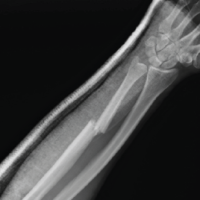

A woman in her 30s from South Asia presented to our tertiary orthopedic unit with persistent pain, restricted range of motion, and functional impairment in her left upper limb. These symptoms had been present for several months following surgical fixation of a distal humerus intercondylar fracture sustained after a fall on an outstretched hand while descending stairs. At the time of injury, she was evaluated at a local trauma center, where radiographs revealed a displaced intercondylar distal humerus fracture with a concurrent fracture of the proximal shaft of the ipsilateral ulna (Fig. 1). She underwent open reduction and internal fixation using dual plating for the distal humerus and plating for the ulnar fracture (Fig. 2). The limb was immobilized in a splint for 10 days, followed by supervised physiotherapy. The ulnar fracture showed progressive healing and achieved union by 3 months post-operatively.

Figure 1: Pre-operative 3D computed tomography reconstructions showing a displaced intercondylar fracture of the distal humerus with associated ipsilateral proximal ulnar shaft fracture.

Figure 2: Immediate post-operative anteroposterior and lateral radiographs showing stable dual-plate fixation of the distal humerus with associated plate fixation of the ipsilateral ulna.